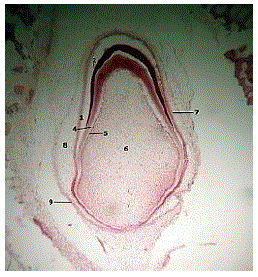

Analise a figura de um germe dentário.

Sobre este germe dentário, analise as afirmativas a seguir.

I. A figura representa um germe dentário na fase de botão, onde há maior atividade de morfogênese e diferenciação.

II. A figura apresenta a papila dentária, responsável pela formação dos odontoblastos.

III. O desenvolvimento do germe dentário ocorre em 5 fases: botão, capuz, campânula, coroa e raiz.

IV. Em todas as fases do germe dentário, a Bainha de Hertwig estará presente.

Marque a opção que apresenta as afirmativas CORRETAS.